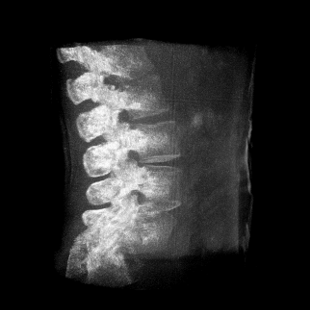

術(shù)中三維成像和橫斷面圖像提供多角度的手術(shù)診斷信息,輔助醫(yī)生進(jìn)行術(shù)中評(píng)估判斷,諸如骨折復(fù)位情況和內(nèi)植入螺釘?shù)某叽绾臀恢茫o助手術(shù)更好地完成。

提供更大的術(shù)中三維成像視野,采集更多圖像信息,可一次拍全全段頸椎、全段腰椎、七節(jié)胸椎、雙側(cè)骶髂關(guān)節(jié)、股骨頭及單側(cè)盆骨。